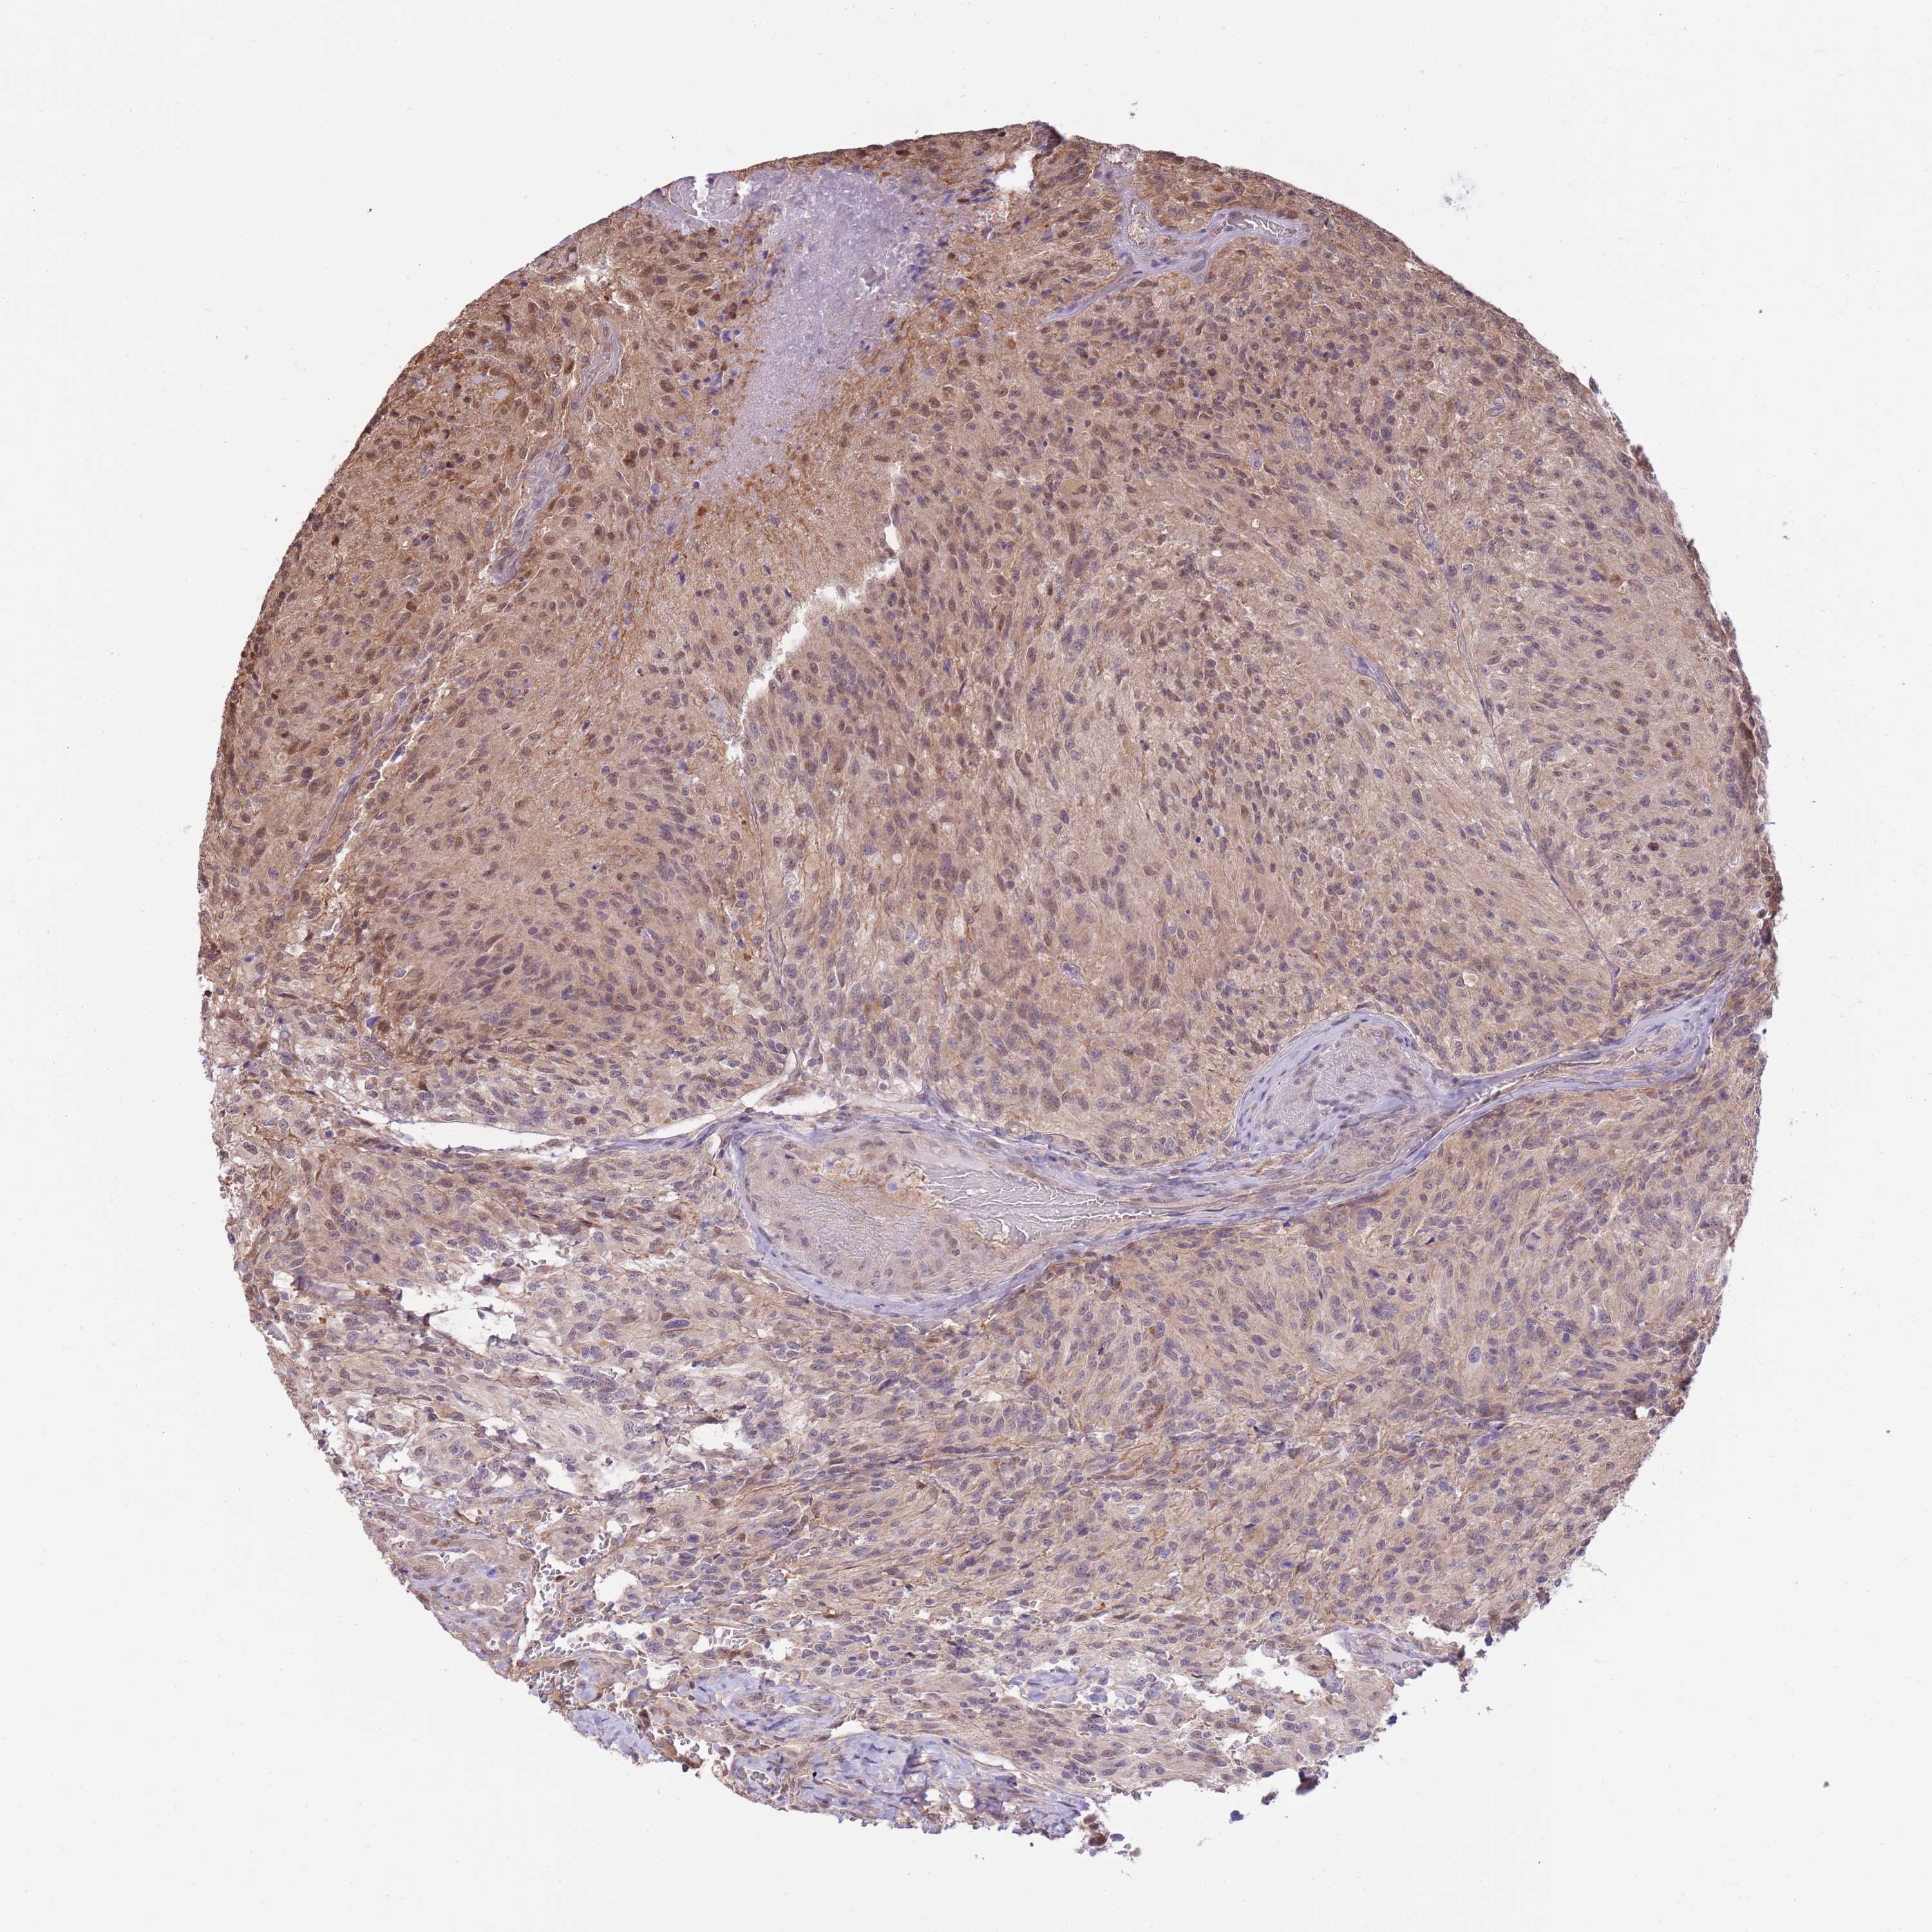

GLIOMA - Protein expressioni

A mouse-over function shows sample information and annotation data. Click on an image to view it in a full screen mode. Samples can be filtered based on level of antibody staining by selecting one or several of the following categories: high, medium, low and not detected. The assay and annotation is described here.

Note that samples used for immunohistochemistry by the Human Protein Atlas do not correspond to samples in the TCGA dataset.

Antibody stainingi

Antibody staining in the annotated cell types in the current human tissue is reported as not detected, low, medium, or high, based on conventional immunohistochemistry profiling in selected tissues. This score is based on the combination of the staining intensity and fraction of stained cells.

Each image is clickable and will lead to virtual microscopy that enables deeper exploration of all samples and also displays staining intensity scores, fraction scores and subcellular localization as well as patient and tissue information for each sample.

Antibody HPA047108

Antibody HPA050628

Staining

High

Medium

Low

Not detected

Intensity

Strong

Moderate

Weak

Negative

Quantity

>75%

75%-25%

<25%

None

Location

Nuclear

Cytoplasmic/membranous

Cytoplasmic/membranous,nuclear

Glioma, malignant, High grade

Glioma, malignant, Low grade